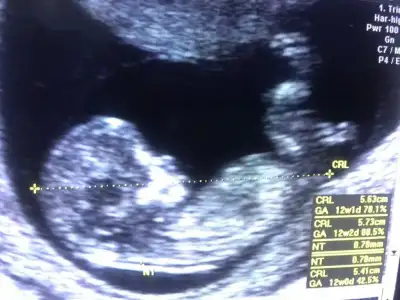

Kızlar merhaba 12 hafta cinsiyet tahmini yapabilcek olan var mı 😁

• image.webp

image.webp

45,1 KB · Görüntüleme: 69